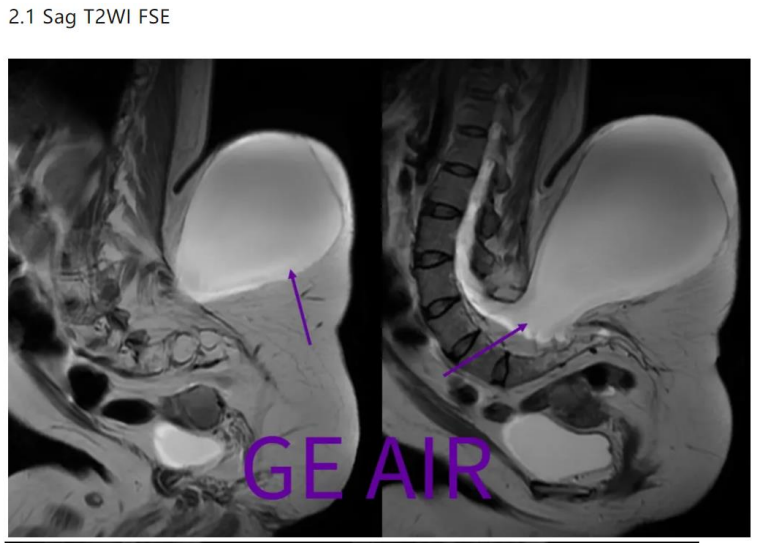

北京的专家主要想看这个囊肿的结构,以及与周围组织的关系,申请磁共振平扫。兄弟单位磁共振室由于患者无法平躺而婉拒,现来我院试试最新的3T磁共振。 患者家属还带了一些图片(可能引起不适):

直角体位是该患者最舒适的。所以兄弟单位的MR科室,拒绝了这个患者的扫描请求。 二、劝退? 劝退,当然很容易。毕竟兄弟单位已经,毕竟患者很多很多,毕竟医院还有绩效考核。。。。 要么试试AIR包裹线圈吧

回顾性翻看矢状面T2和T2 fs,由于椎管内脂肪(红箭)和脑脊液交界,化学位移现象很重,所以干扰了囊性包膜的显示。